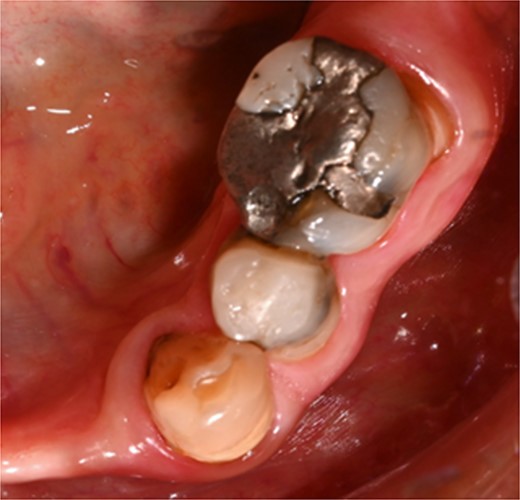

A 44-year-old patient presented to our clinic with the primary complaint of food lodgment in a cavity on the lower left posterior teeth. Clinical examination revealed extensive caries on the disto-occlusal surface of the lower left first permanent molar (tooth 36) (Fig. 1). Radiographic examination showed a large radiolucency at the distal crown extending to the cervical third of the distal root, with periapical radiolucencies on both mesial and distal roots (Fig. 2). The tooth was diagnosed with asymptomatic irreversible pulpitis and symptomatic apical periodontitis.

Clinical photograph of tooth 36 showing extensive caries on disto-occlusal surface.